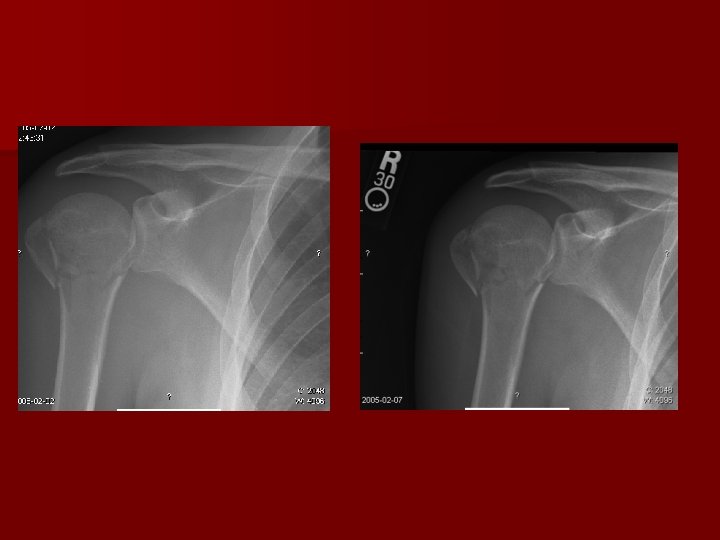

Shoulder Dislocations n Clinical Evaluation – Examine axillary nerve (deltoid function, not sensation over lateral shoulder) – Examine M/C nerve (biceps function and anterolateral forearm sensation) n Radiographic Evaluation – – True AP shoulder Axillary Lateral Scapular Y Stryker Notch View (Bony Bankart)

Shoulder Dislocations n Anterior Dislocation Recurrence Rate – – – n Age 20: 80 -92% Age 30: 60% > Age 40: 10 -15% Look for Concomitant Injuries – Bony: Bankart, Hill-Sachs Lesion, Glenoid Fracture, Greater Tuberosity Fracture – Soft Tissue: Subscapularis Tear, RCT (older pts with dislocation) – Vascular: Axillary artery injury (older pts with atherosclerosis) – Nerve: Axillary nerve neuropraxia

Shoulder Dislocations n Posterior Dislocation – Adduction/Flexion/IR at time of injury – Electrocution and Seizures cause overpull of subscapularis and latissimus dorsi – Look for “lightbulb sign” and “vacant glenoid” sign – Reduce with traction and gentle anterior translation (Avoid ER arm Fx)

Shoulder Dislocations n Postreduction – Post reduction films are a must to confirm the position of the humeral head – Pain control – Immobilization for 7 -10 days then begin progressive ROM n Operative Indications – – Irreducible shoulder (soft tissue interposition) Displaced greater tuberosity fractures Glenoid rim fractures bigger than 5 mm Elective repair for younger patients